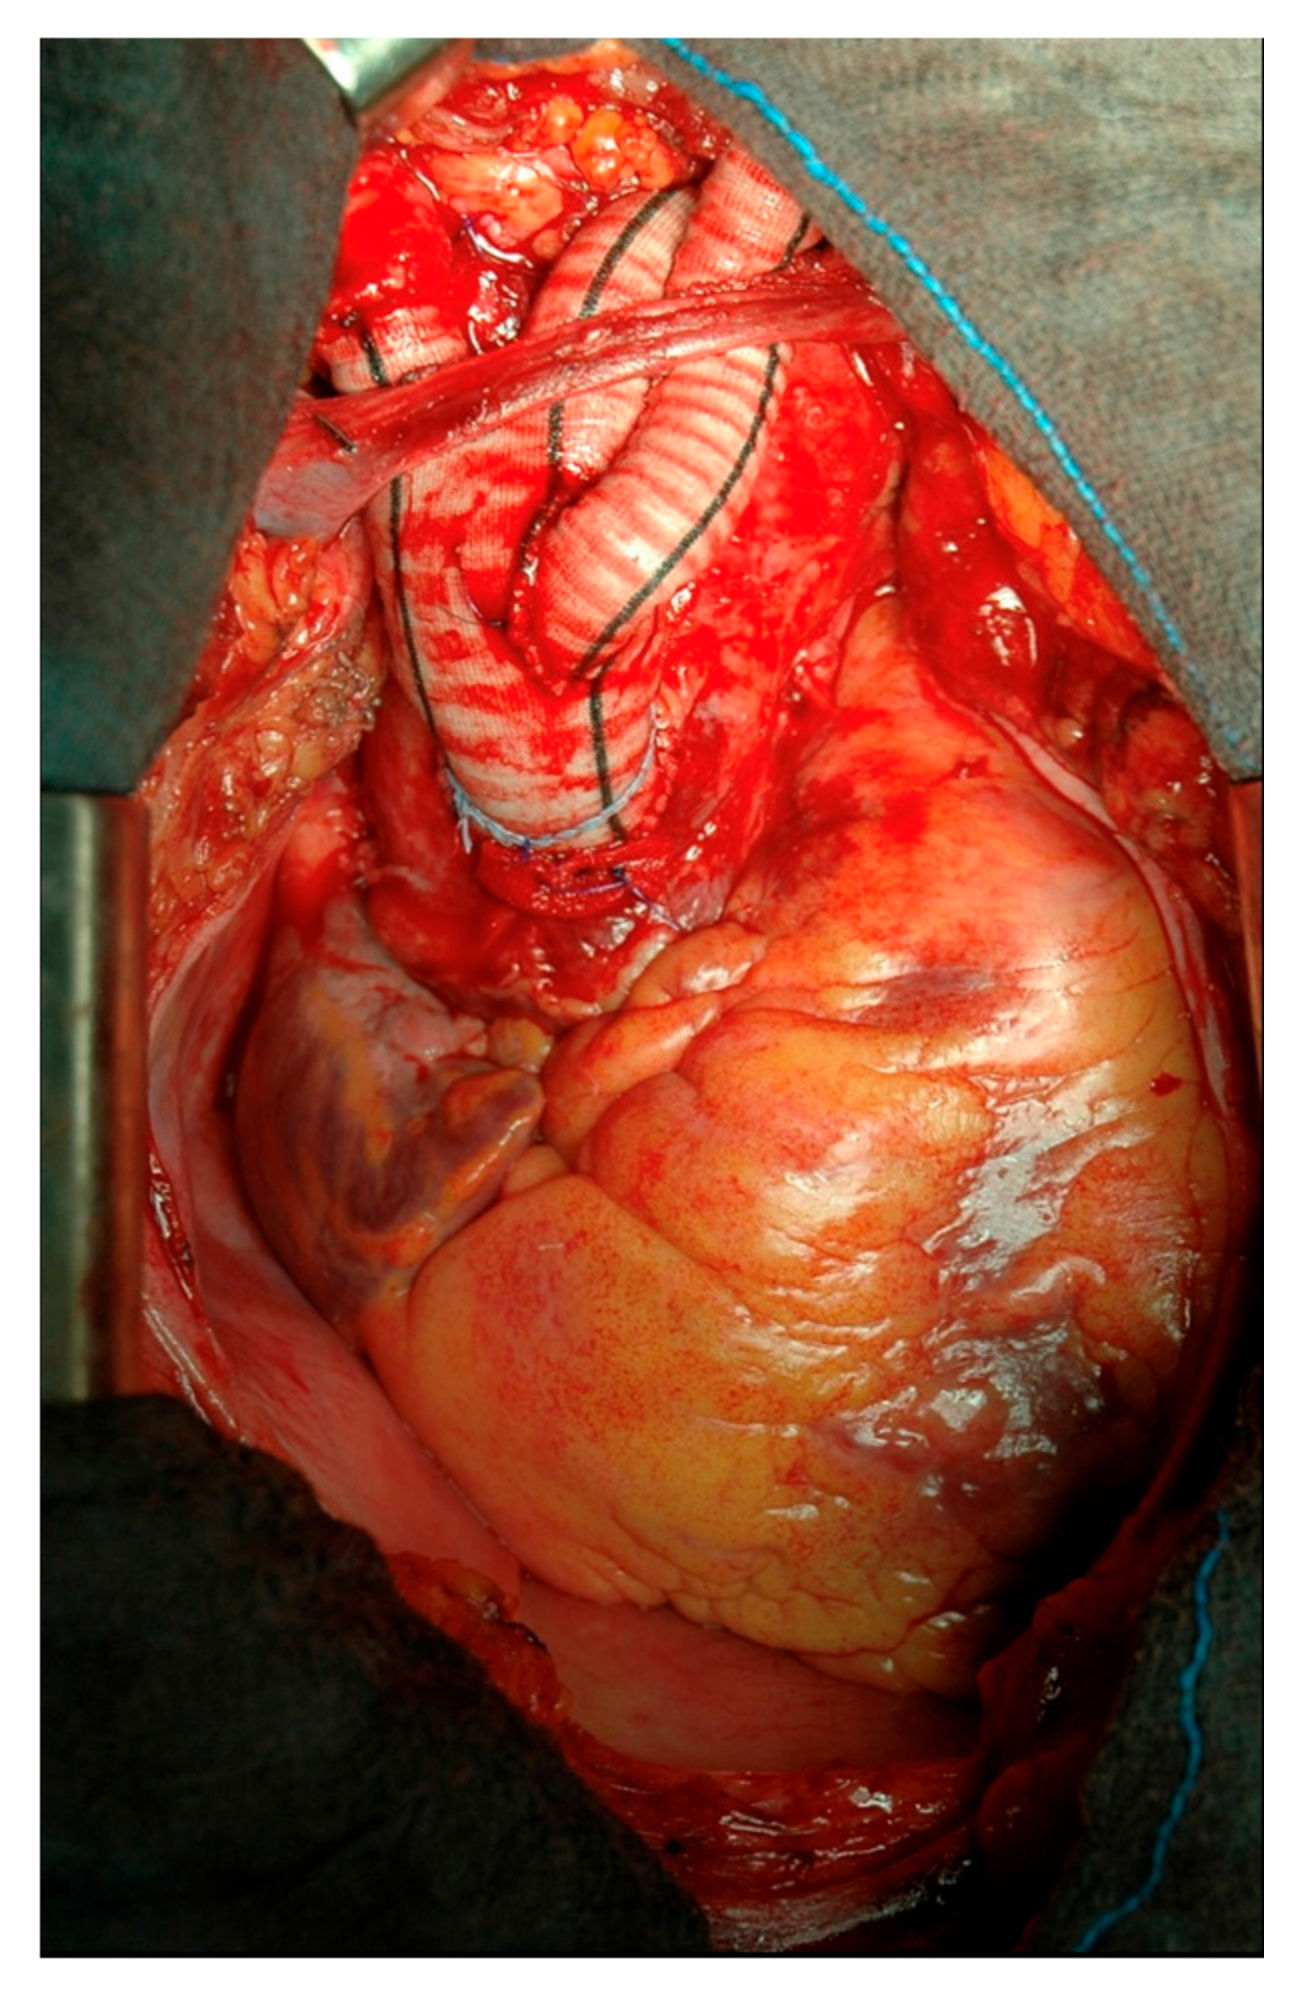

2.1. Surgical Technique

2.2. Type I Debranching

2.3. Type II Debranching

2.4. Branched Graft Position

2.5. Left Subclavian Artery Debranching